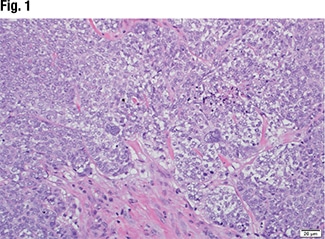

Dr. Graham displayed the image of a tissue specimen from a similar case (Fig. 1). “We have a neoplasm characterized by moderate-sized neoplastic cells with focal chromatin, prominent macronucleoli. And there are some occasional cells that show severe nuclear pleomorphism and multi-nucleation.” He also pointed out a brisk mitotic rate and some foci of necrosis. “A tumor that has a nonspecific look, such as this, is something we encounter rather frequently in our practice.”